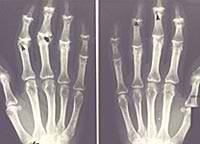

Investigadores españoles descubren una alteración genética producida en la mitocondria relacionada con la artrosis

Este descubrimiento es el primero a nivel mundial que demuestra una susceptibilidad genética en el ADN mitocondrial.